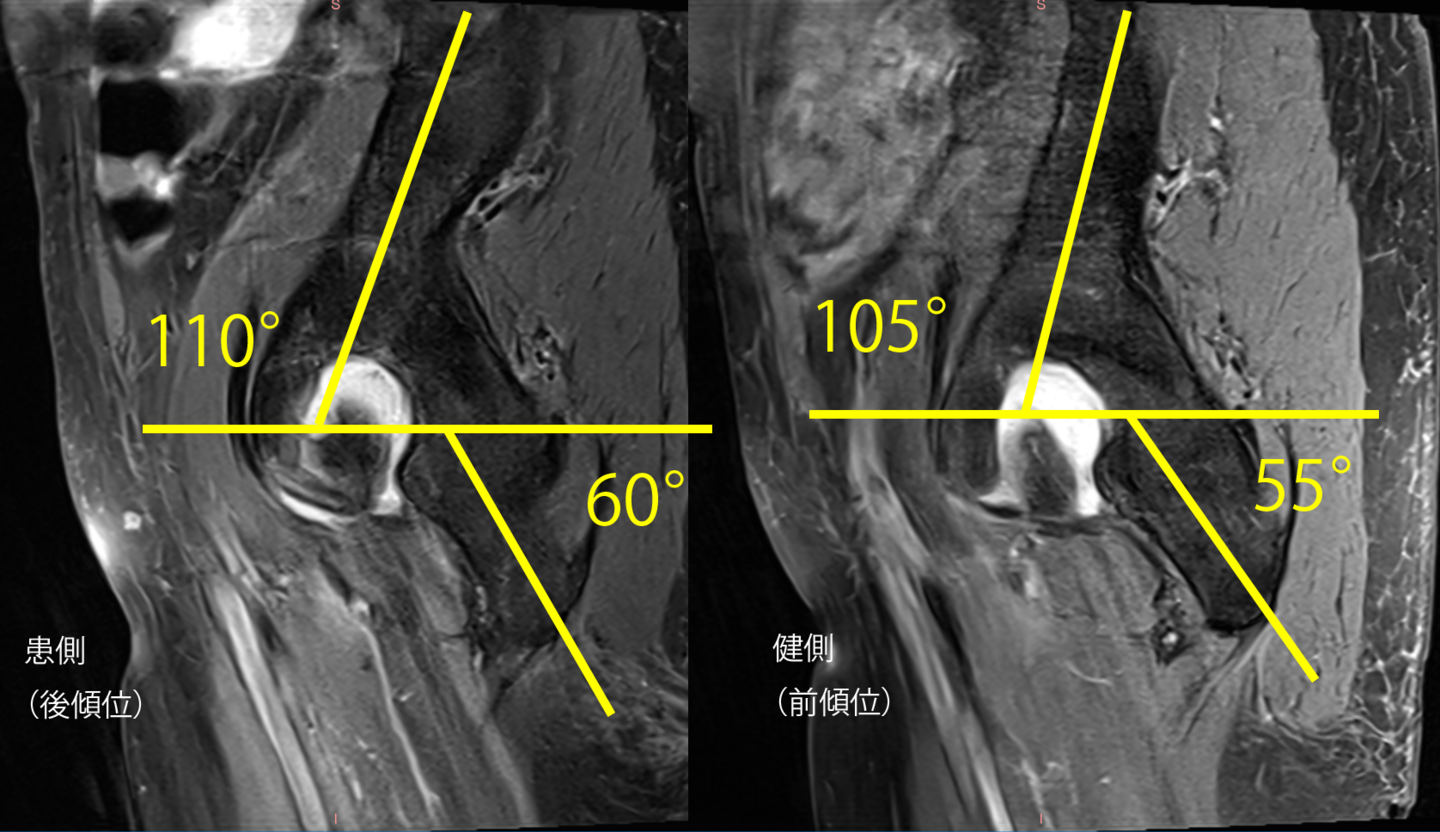

3Dモデリングで痛みや動きを分析

病態を理解し、適切な治療を行うためには、関節の構造を理解し、体の深部に影響を与えることが出来なければなりません。そのためにも3Dモデリングを使うことが非常に役に立つことがわかりました。もし画像所見をお持ちでしたらお借りできますと幸いです。

MRI画像の様に、骨盤と仙骨の位置関係がズレる事で症状が発生していきます。

腰部の前後傾(猫背・反り腰)や股関節の可動域制限も関与し、場合によっては痺れなどの神経障害の原因にも繋がる事がある為、「関節・筋肉・神経」を改善し、症状の緩解を目指します。